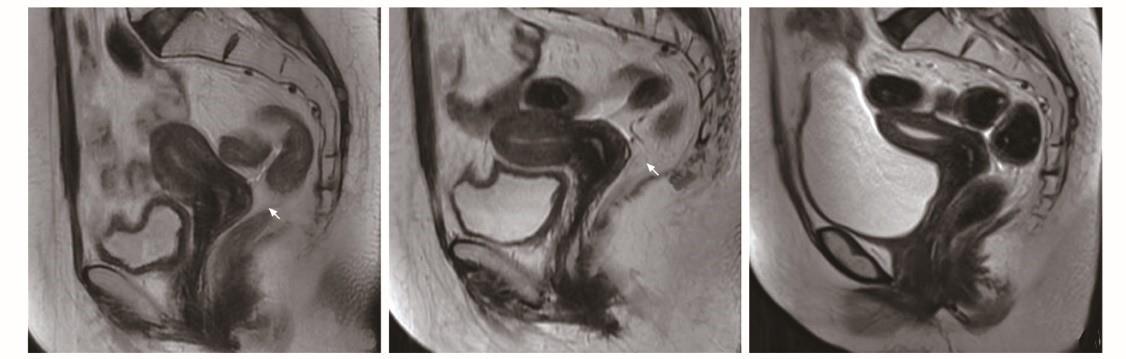

患者放疗后盆腔MRI图像A.放疗26次后宫颈环周略长T2高信号(箭头);B.放疗后1个月宫颈T2信号较前降低(箭头);C.放疗后4个月宫颈未见异常信号

原以为要和放疗来场痛苦折磨的“拉锯战”,但1个月28次的在线自适应放疗很快就过去了。丽屏做梦都想不到,她的宫颈占位性病变相较之前明显缩小。紧接着是近半个月的三维近距离放疗5次,和外照射期间同步顺铂增敏化疗共6程。随着治疗的深入,她的身体状态也越来越好了。

治疗结束后的1个月、4个月,丽屏身上没有任何复发转移的情况出现。更值得庆贺的是,在所有放疗过程中,她只出现过轻微腹泻,没有出现过血液学、泌尿生殖系统及其他放疗的相关不良反应。